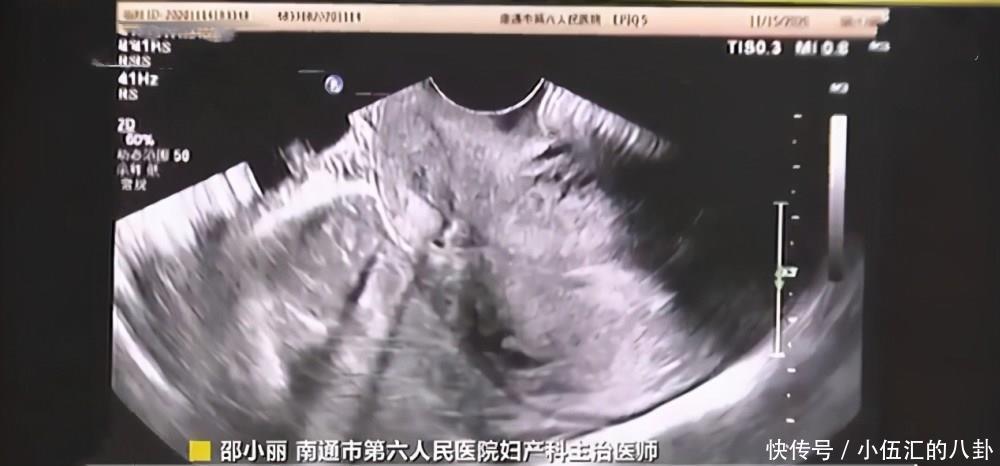

“考虑是宫内孕合并卵巢妊娠”,医生解释,经自然受孕而发生一胎在宫内、另一胎在宫外的几率只有1/10000-3/10000。为此,王女士因为这一罕见怀孕在“鬼门关”走了一趟。